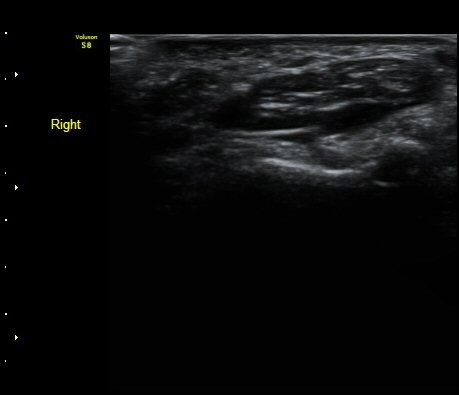

¼ÒÁö±¸ ³»Ãø¿¡ ȾÀ¸·Î ŽÃËÀÚ¸¦ ´ë¾î °¥°í¸®»À °¥°í¸® ³»Ãø¸é ÇÇÁú°ñÀ» °üÂûÇÏ´Ï(¾Æ·¡ ±×¸²)

°¥°í¸® ÇÇÁú°ñ ¿¬¼Ó¼º ¼Ò½Ç(loss of cortical continuity of hook of hamate)ÀÌ °üÂûµÈ´Ù(±×¸² 1, 2).

ÇÇÁú°ñ ¿¬¼Ó¼º ¼Ò½ÇÀº °ÇÃø°ú ºñ±³ÇØ¸é ´õ¿í ¶Ñ·ÈÇÏ´Ù(±×¸² 3, 4).